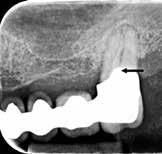

Fig. 1. A. Udsnit af panoramaoptagelse viser Ca(OH)2 uden for foramen apicale i en overkæbemolar og i sinus maxillaris (pil). B. Periapikal optagelse viser Ca(OH)2 uden for foramen apicale (pil) i en central incisiv. Tilfældet krævede kirurgisk indgreb.

Fig. 1 A. An orthopantomography section showing Ca(OH)2 beyond the apical foramen of maxillary first into the maxillary sinus (arrow) and (B) a periapical radiograph with Ca(OH)2 extrusion beyond the apical foramen (arrow) of a central incisor which required surgical intervention.

Ved mistanke om malpraksis vurderer man behandlerens handlinger i alle stadier i relation til opgavens kompleksitet og tager stilling til, om disse lever op til normen for almindelig anerkendt faglig standard. De mest omfattende skadevirkninger ses i forbindelse med anvendelse af endodontiske skyllevæsker og andre medikamenter, fx ulykker med natriumhypoklorit eller skader på nervevæv eller i sinus som følge af udpresning af calciumhydroxid igennem foramen apicale (Fig. 1A og B) (5,6). Sådanne uheld vurderes ofte til at være undgåelige, idet tandlægen ikke har levet op til normal faglig standard. Frygt for at begå procedurefejl eller andre utilsigtede hændelser bør dog ikke få klinikeren til helt at afstå fra at foretage endodontiske behandlinger (7).